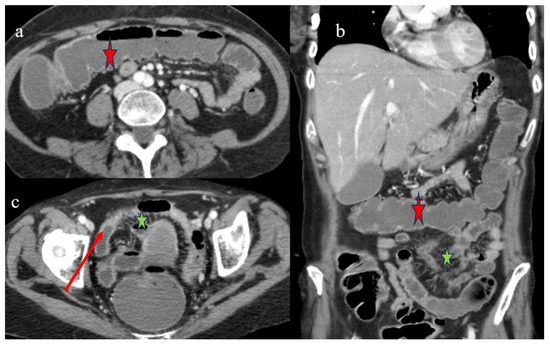

| 4 | P | P | Intestinal diffuse homogeneous thickness with homogeneous mucosal enhancement (on CECT control at 66 days after the HSCT); diffuse small bowel involvement with increased parietal thickness on CECT control at 120 days | Appearance of multisegmental thickness on sigma and descending colon and stratified enhancement on transverse colon on the CT FU at 120 days | Diffuse comb sign and poor reactive mesenteric lymph node | Mild gallbladder thickness and persistence of biliary tract dilatation on follow-up CT |